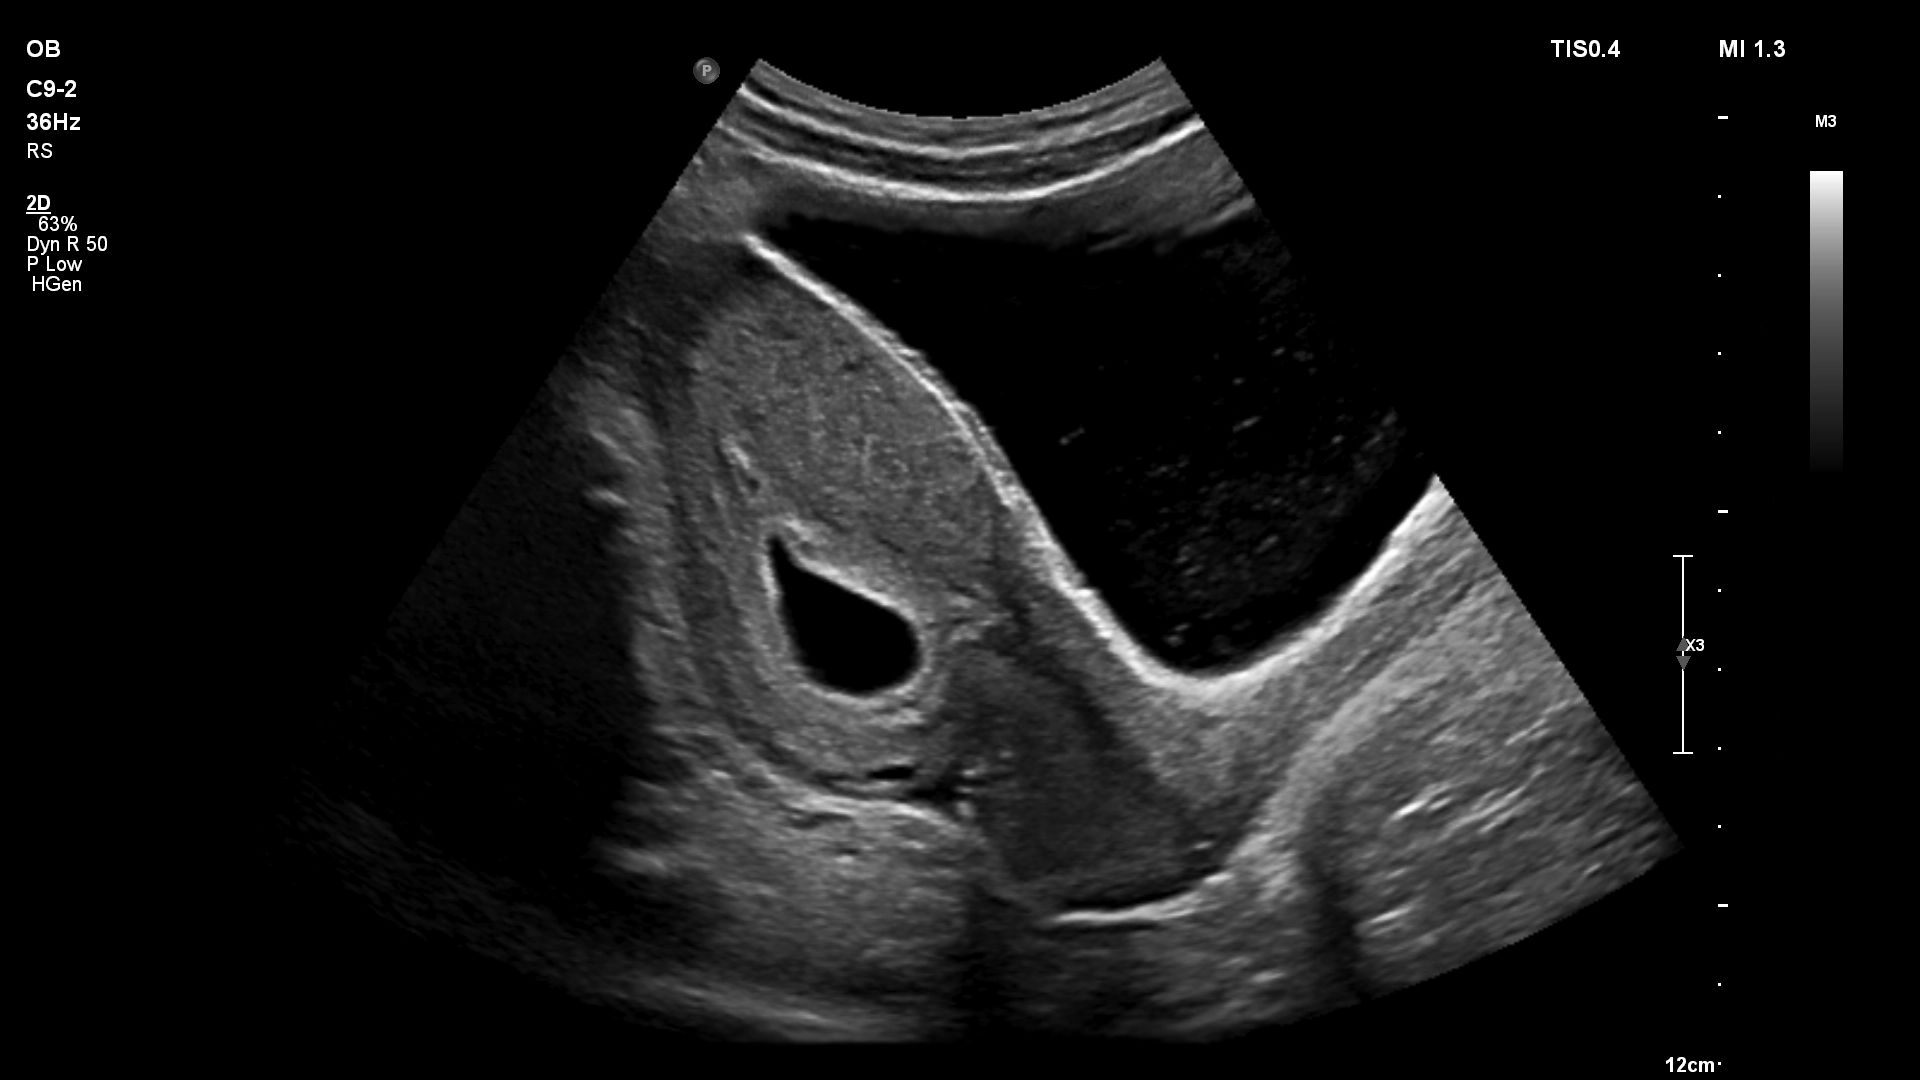

- Акушерство

- Гинекология и фертильность

Функции для гинекологии и акушерства

- Free Hand 3D - возможность реконструкции 3D изображения при помощи линейного или конвексного датчика

- 4D Imaging - автоматическая визуализация 3D/4D изображения